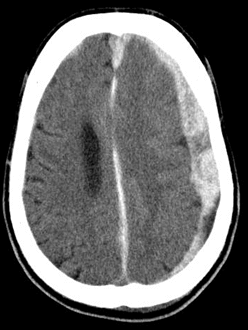

Subdural hematoma is common in chronic alcoholics as well as the elderly after a fall. It is often due to laceration of the bridging veins that connect the dura and arachnoid. The CT scan appearance of the hematoma is “crescent-shaped”.